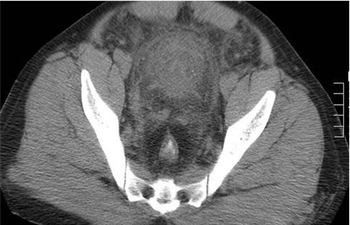

A 40-year-old male presented at the ER with chest discomfort and tacchypnia. No abnormal radiological findings could be detected on the chest X-ray. On examination ischemic changes on the right lower limb, with ECG changes were noted.